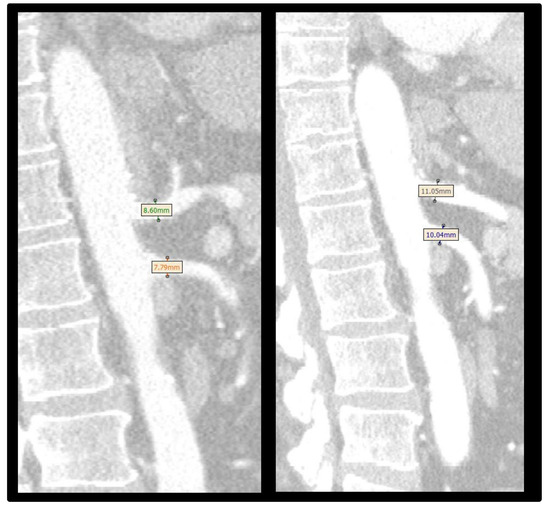

3.5. Abdominal Aortic Branch Adaptation in Patient with Mesenteric Ischemia